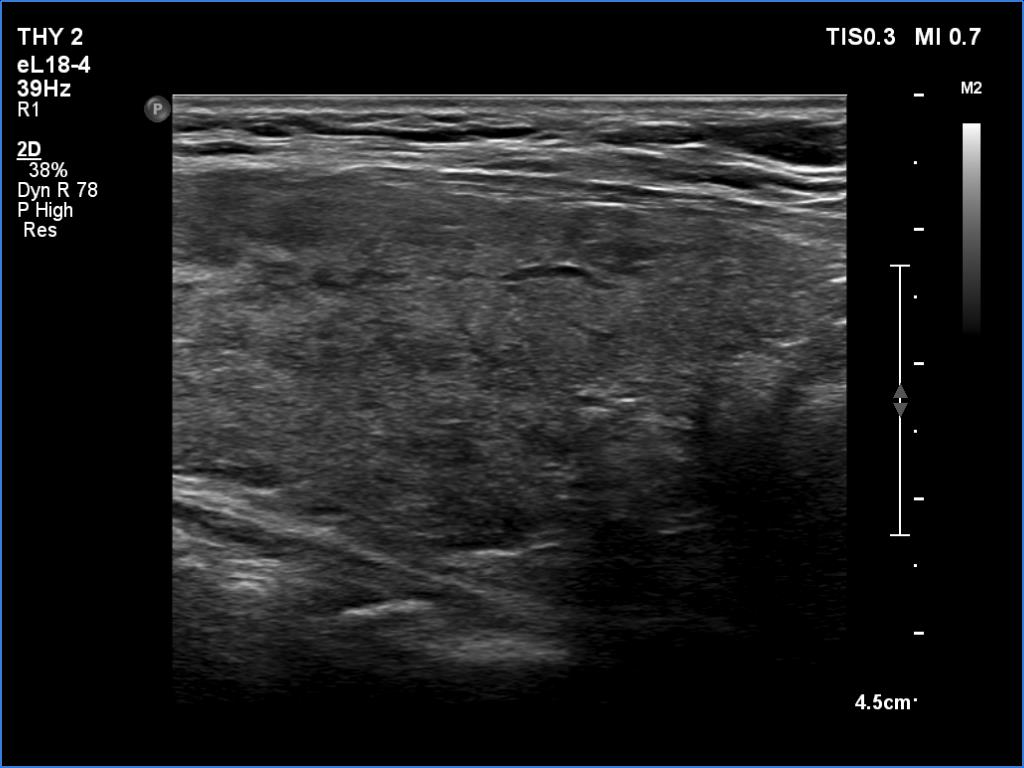

The echogenicity of the nodule - case 2151

Three years after the first examination (ultrasonographic picture 7)

Left lobe, longitudinal scan.